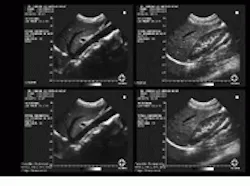

One medical application benefiting from image reconstruction is speckle-noise reduction in the ultrasound imaging of lesions and cancerous tumors. Speckle noise is the primary factor that limits the contrast resolution in diagnostic ultrasound imaging. It limits the detection of small low-contrast lesions and makes ultrasound images generally difficult for all but specialists to interpret.

Recognizing this fact, Lawrence J. Busse, a consultant and founder of L. J. B. Development (Fort Wright, KY), has developed a geometric filtering (GF) algorithm for speckle-noise reduction that allows general medical personnel to readily interpret ultrasound images without the need for a specialist. He developed the algorithm while working as director of research for Tetrad Corp. (Denver, CO), under a grant from the US National Cancer Institute.

The algorithm runs on an AL860 dual-processor board from Alacron Inc. (Nashua, NH) using a frame grabber and a personal computer. (Alacron now also offers more powerful boards based on the Analog Devices Sharc DSP). Using commercially available signal-processing hardware, the algorithm processes and displays ultrasound image frames obtained from a Tetrad E/U2200 ultrasound imaging system at close to 2 frames/s. "With the powerful processor boards available today, I`m sure we can do a lot better in terms of frame rate," notes Busse.

The GF nonlinear iterative algorithm is also being used to reduce noise in binary images and synthetic-aperture-radar (SAR) images. However, when it was applied to images of anatomical features, the algorithm`s effectiveness in reducing speckle noise was determined by the field of view of the scanned image or the spatial sampling range of the image. Images scanned with a small field of view (that is, at a high spatial sampling rate) required many iterations of the algorithm. However, images with a large field of view (that is, a low spatial sampling rate) appeared to be oversmoothed following only a single GF iteration.

Busse set about linking the spatial sampling rate to the actual spatial resolution in ultrasound data to optimally obtain the highest spatial resolution with the fewest GF iterations. He developed a model of the lateral and axial resolutions. The model was developed as a function of transducer geometry, center frequency, and RF processor to determine the data and video sampling rates that should be applied before GF application. Upon usage, this model obtained effective speckle-noise reduction with a single GF application (see Fig. 1).

FIGURE 1. A geometric filtering algorithm developed by Lawrence Busse while at Tetrad Corp. reduces speckle noise in the ultrasound medical images of internal human organs. In one example, an original image of a scanned abdomen shows the liver and its surrounding area (upper left). The same image is reconstructed after applying geometric filtering (lower left). In another example, an original image depicts a kidney (upper right). The same image is restored via geometric filtering (lower right).